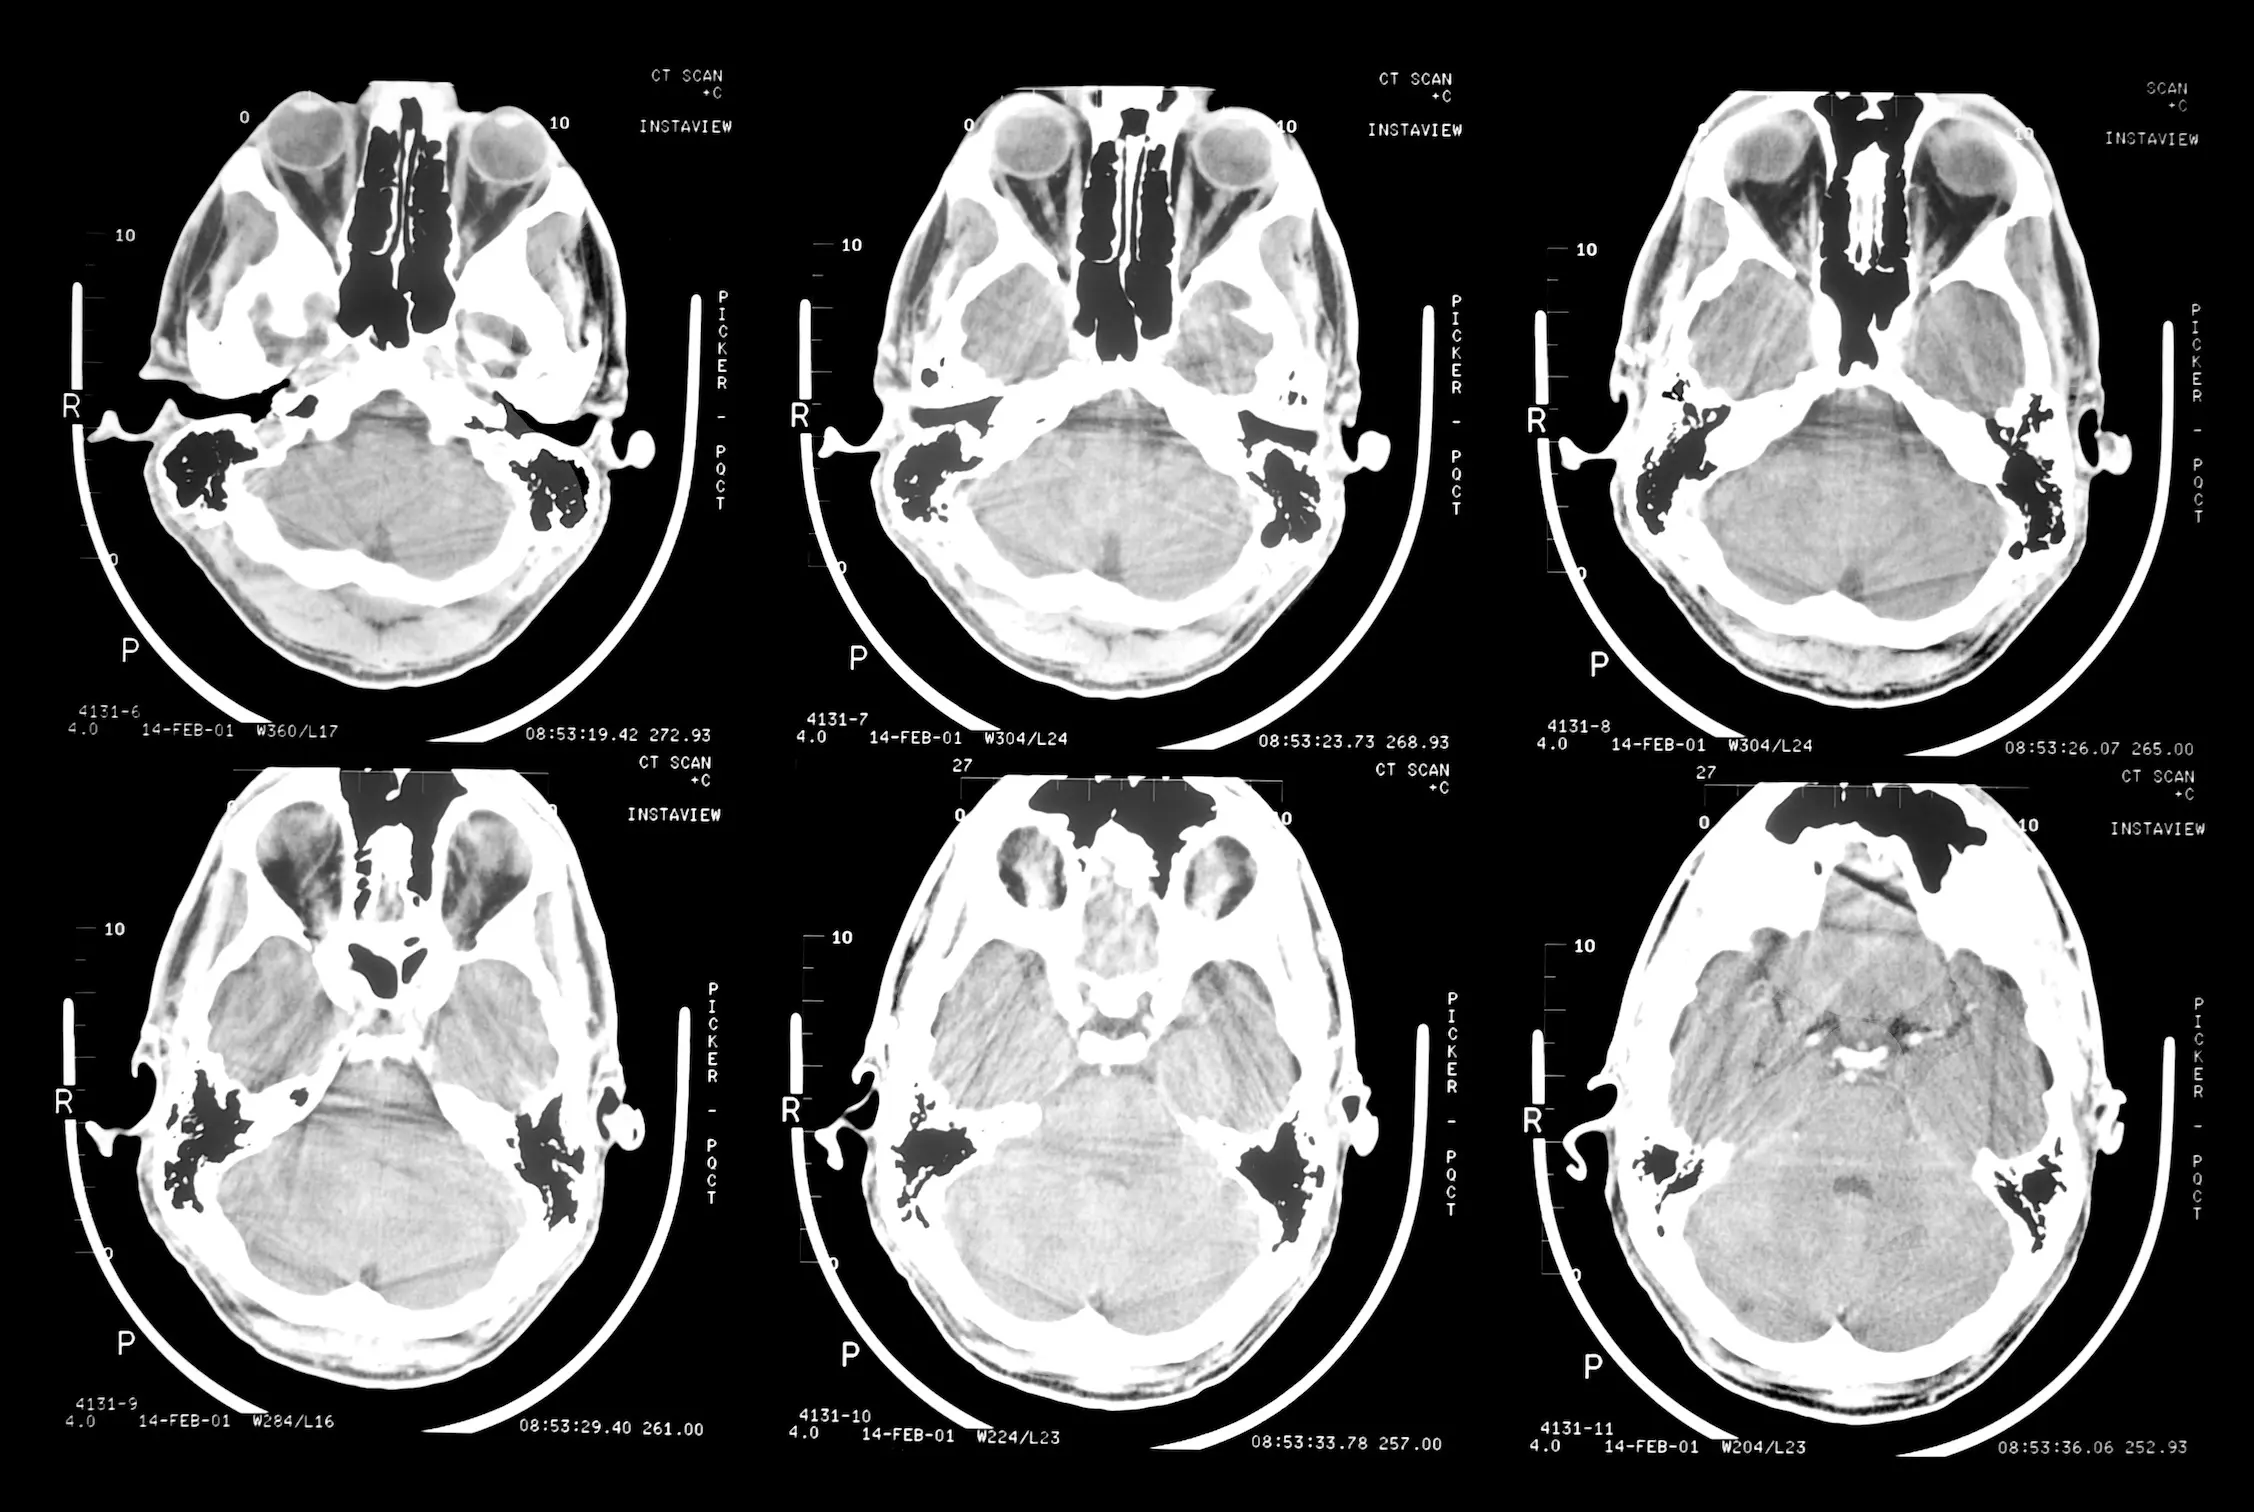

L'épilepsie est une maladie neurologique très répandue en Afrique (photo d'illustration)